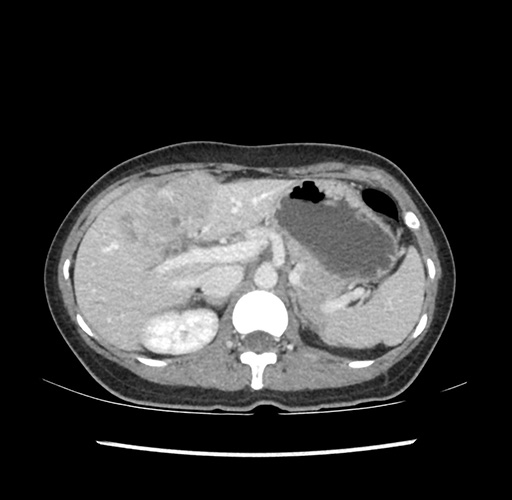

Imaging Analysis

Look through the patient's CT scan to identify any areas of concern for the necessary procedure.

Based on your CT findings, which issue(s) would give reason for "planned slowing down moment(s)" in this case?